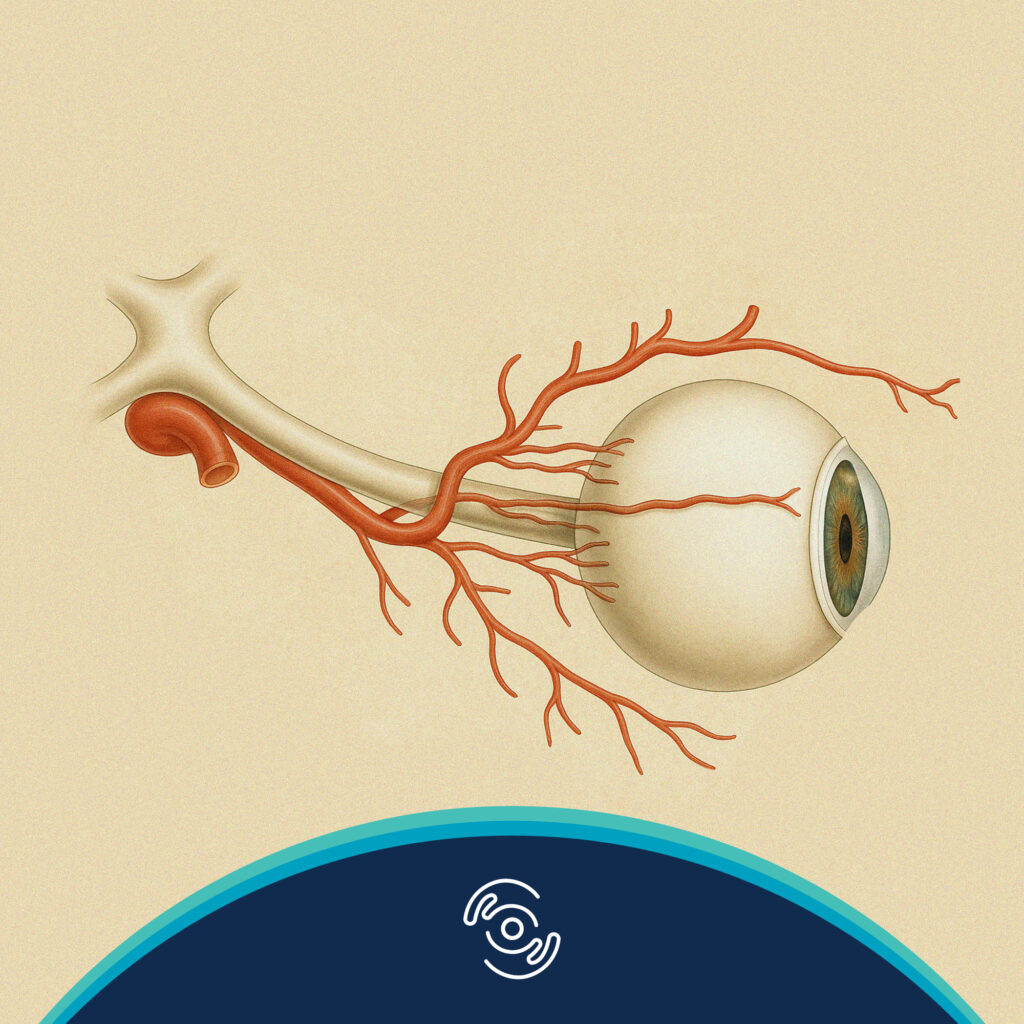

Duong, HV. Eye Globe Anatomy. Medscape Reference. Updated 9 November 2017.

Duong, HV. Visual System Anatomy. Medscape Reference. Updated 9 November 2017.

Duong, HV, Copeland, RA. Arterial Supply to the Orbit. Medscape Reference. Updated 20 October 2017.